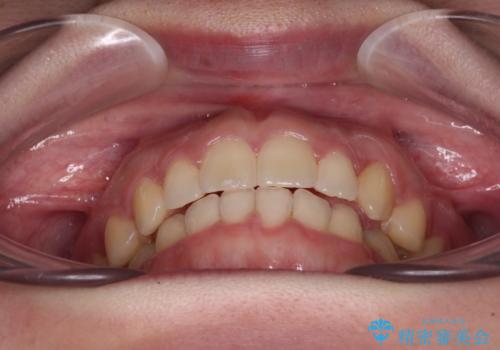

気になる残存乳歯と八重歯 ワイヤー矯正を併用したインビザライン治療

- 八重歯を気にして来院された患者様です。

八重歯のために乳歯が残存していたため、乳歯を抜去して八重歯となっている犬歯を歯列に収めることとしました。

八重歯の移動量が多くなるため、インビザラインと併用してワイヤー矯正を行い、八重歯を改善した後に、上下歯列をインビザラインで整えることとしました。

犬歯は歯根が長くて太いため移動に時間がかかる上に、周囲の歯が八重歯に寄ってきてしまうため、仕上がるまでに期間がかかりました。